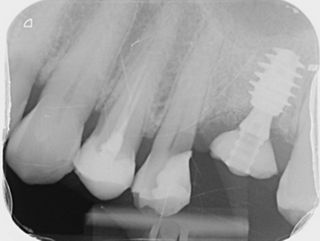

14a. 14b. Radiograph of 2 years follow-up.

14a

14b